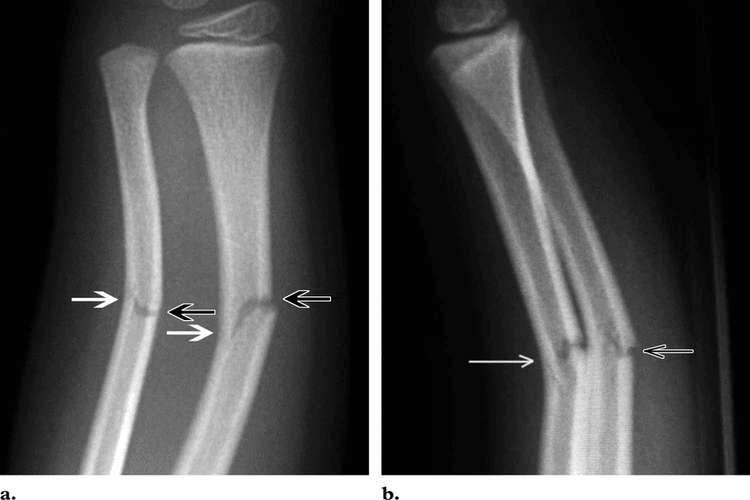

Greenstick Fracture - एका बाजूने फ्रॅक्चर, पण हाड वाकल्याने ते पूर्ण न तुटणे. हे फ्रॅक्चर लहान मुलांमध्ये जास्त आढळून येते कारण त्यांची हाडे लवचिक असतात.

Hairline Fracture - अतिशय बारीक फ्रॅक्चर जे कधी कधी एक्स रे मधून दिसत नाही.

Torus Fracture - यात हाड तुटत नाही पण हाडाचा आकार बदलल्याने वेदना होतात.